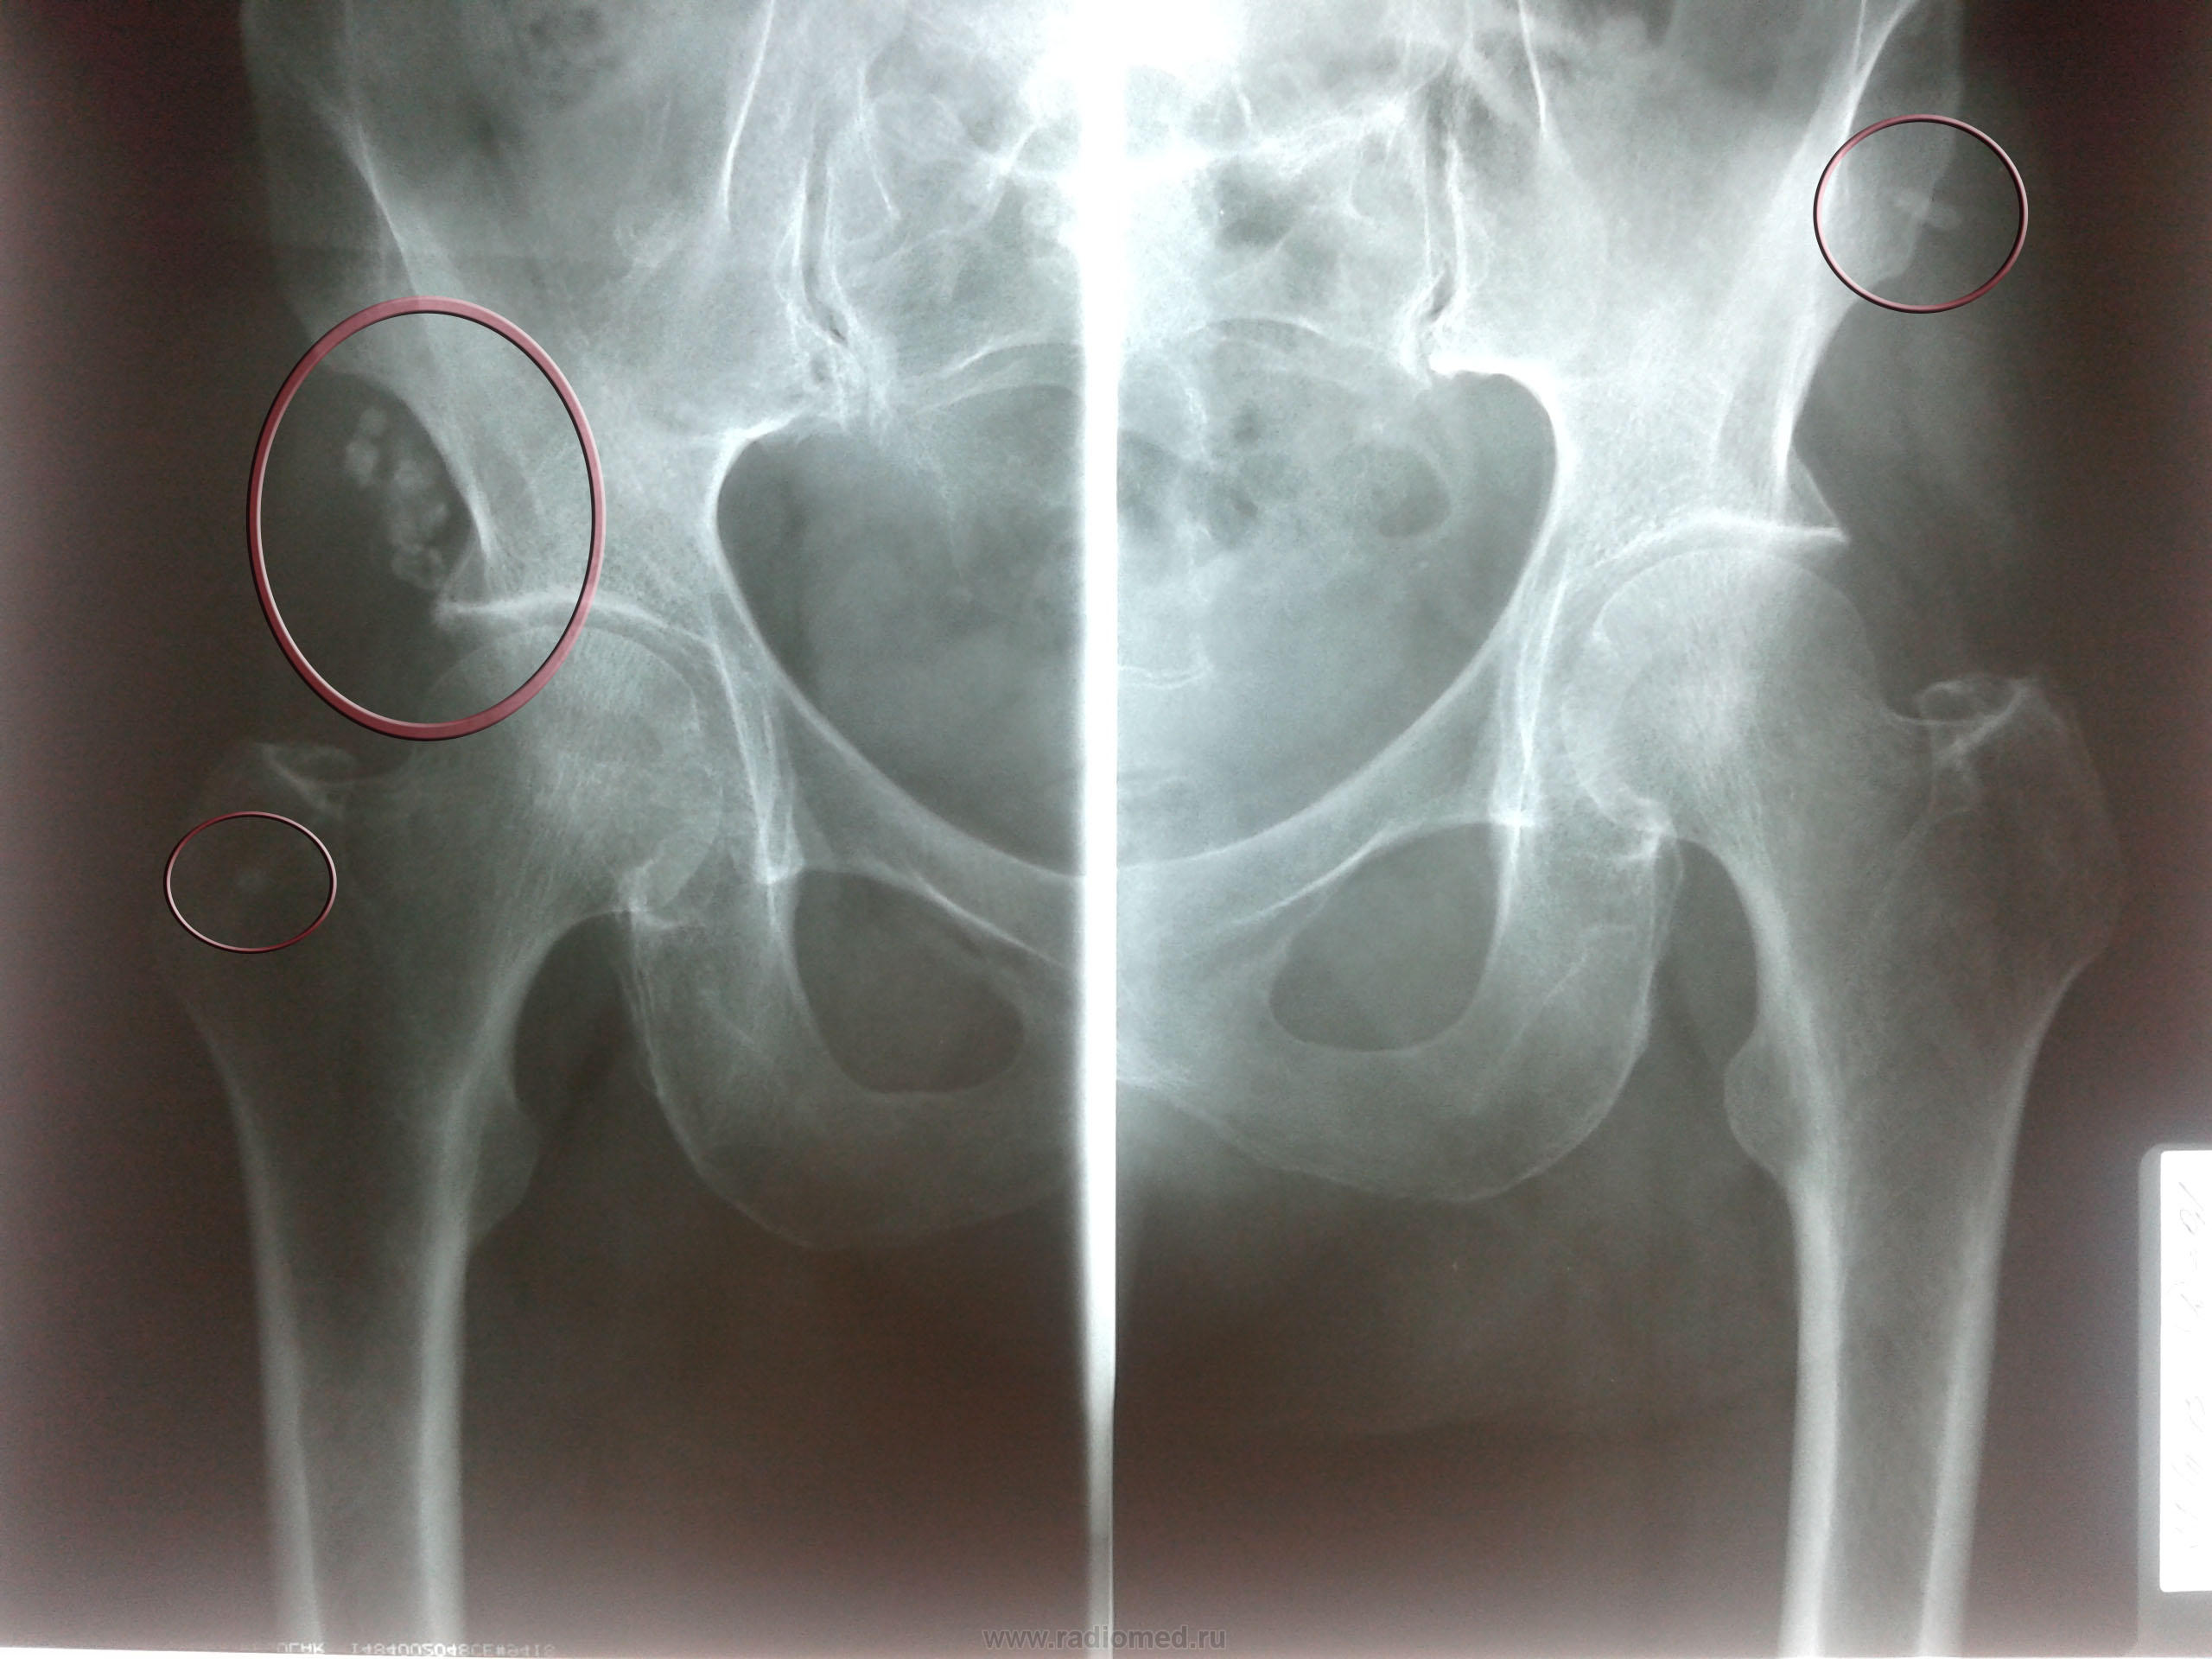

Оссификация тазобедренных суставов: что это и как проявляется?

Раздел: Сокровищница опыта